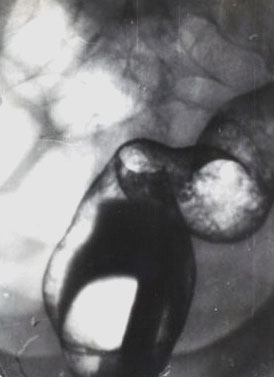

Неспецифический язвенный колит.

Рис. 2. Тот же больной. Поражение прямой и дистального отдела сигмовидной кишки с укорочением, выпрямлением контуров, характерным «зернистым» пневморельефом.

Предоставил Дементьев Е.З.

Радиология-практика 2004 2: 48-56